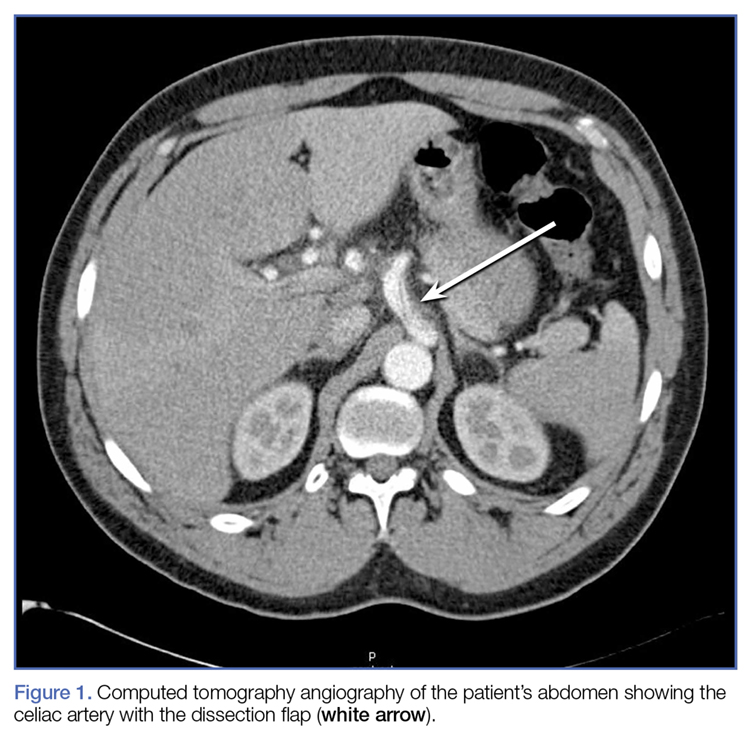

Given the patient’s recent hypertensive episode, a computed tomography angiography (CTA) of the chest and abdomen was also obtained, which revealed an isolated 4.5-cm dissection of the celiac artery (DCA) with filling defect in the hepatic artery (Figure 1).Based on the CTA findings, a nicardipine infusion was immediately started, and the patient was admitted to the medical intensive care unit (MICU). Because his heart rate was in the range of 60 beats/min, an esmolol infusion was not required. Prior to transferring the patient to MICU, a second ultrasound study of the aorta was performed by our fellowship-trained director of emergency medicine ultrasound.